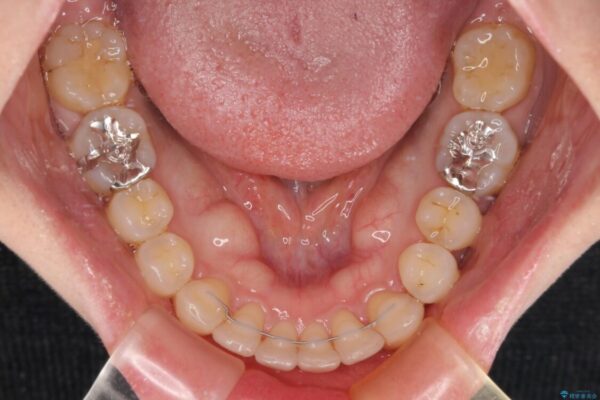

治療前

• 上顎前歯の突出を軽減 インビザラインによる抜歯矯正 治療前画像